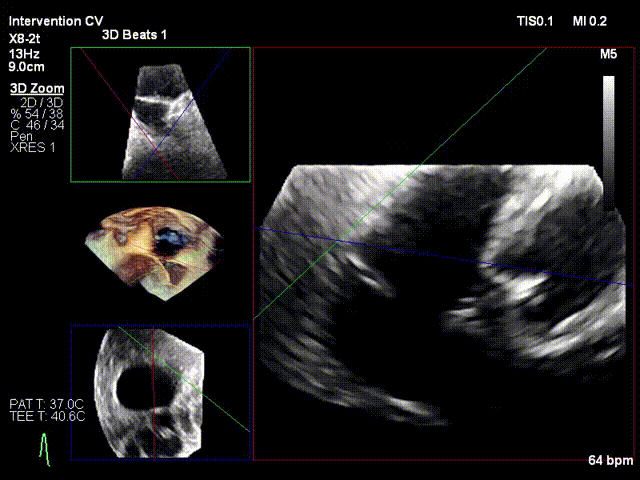

After the patient was placed under general anesthesia, the jugular vein was punctured intraoperatively to establish surgical access. An 18Fr delivery sheath was advanced along a stiff guidewire to the mid-inferior right atrium, and the delivery system was introduced under ultrasound guidance. A 12T K-Clip® device was implanted at the posterior annulus, and another 12T K-Clip® device at the anteroposterior annulus respectively. The angle between the device and the annulus plane was adjusted through catheter deflection and rotation, directing the tip of the clip device to the target position. The anchoring component was deployed into the annulus under ultrasound MPR mode; after confirming stable traction, the clamping arms were opened and apposed to the annulus, followed by retraction of the anchoring component to close the clamping arms for annuloplasty. The surgical effect was evaluated as satisfactory, and the clip components were then released.

Deployment of the anchoring component under the MPR view

Implanting the second clip at the anteroposterior commissure following the same procedure